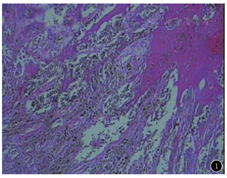

患者 女,59岁。4~5年前无明显诱因下发现右手黑色斑块,约米粒大小,无红肿、痛痒。1年前右手黑斑进行性增大,无触痛,无红肿,无瘙痒,无溃烂。临床检查:右手拇指中节桡侧可见1.2 cm×0.9 cm黑斑,略高于皮面,表面粗糙不平,未见毛发生长、破溃、皲裂及异常分泌物等,皮下尚可推动,未触及粘连固定,周围皮肤无红肿。拇指活动无障碍,肘部滑车淋巴结及腋窝淋巴结未触及肿大。于局部麻醉下行右手皮肤恶性肿瘤扩大切除+任意皮瓣转移修复术,术中见肿块长1.2 cm,宽0.9 cm,先超过肿块边缘3 mm标记切除范围,局部利多卡因浸润麻醉,依据标记线切除右手黑色肿块,深达肌层(标本送快速病理检查)。肿块切除后留下同等大小皮肤缺损,故术中在缺损旁做一个舌形皮瓣,游离周边皮肤以及复合皮瓣,交叉后修复,分层缝合皮下、皮肤。修复右拇指形态、活动基本正常,无明显畸形。快速病理报告为恶性黑色素瘤,建议截肢手术,患者不能接受。术后常规病理报告:右手恶性黑色素瘤,浸润至真皮深层,深度约0.3 cm(图1);侧切缘、底切缘阴性,免疫组化Vimentin、HMB45、S-100、Melan-A均强阳性,CK阴性。术后患者出院赴省级医院进一步扩大手术及后续治疗。